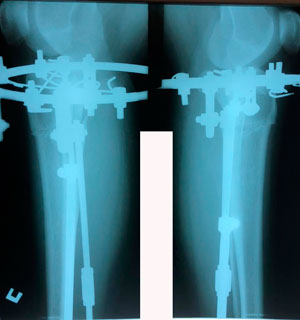

Исходник - 40 лет.

Дата операции - 09.06.2020

в процессе круток

на фиксации